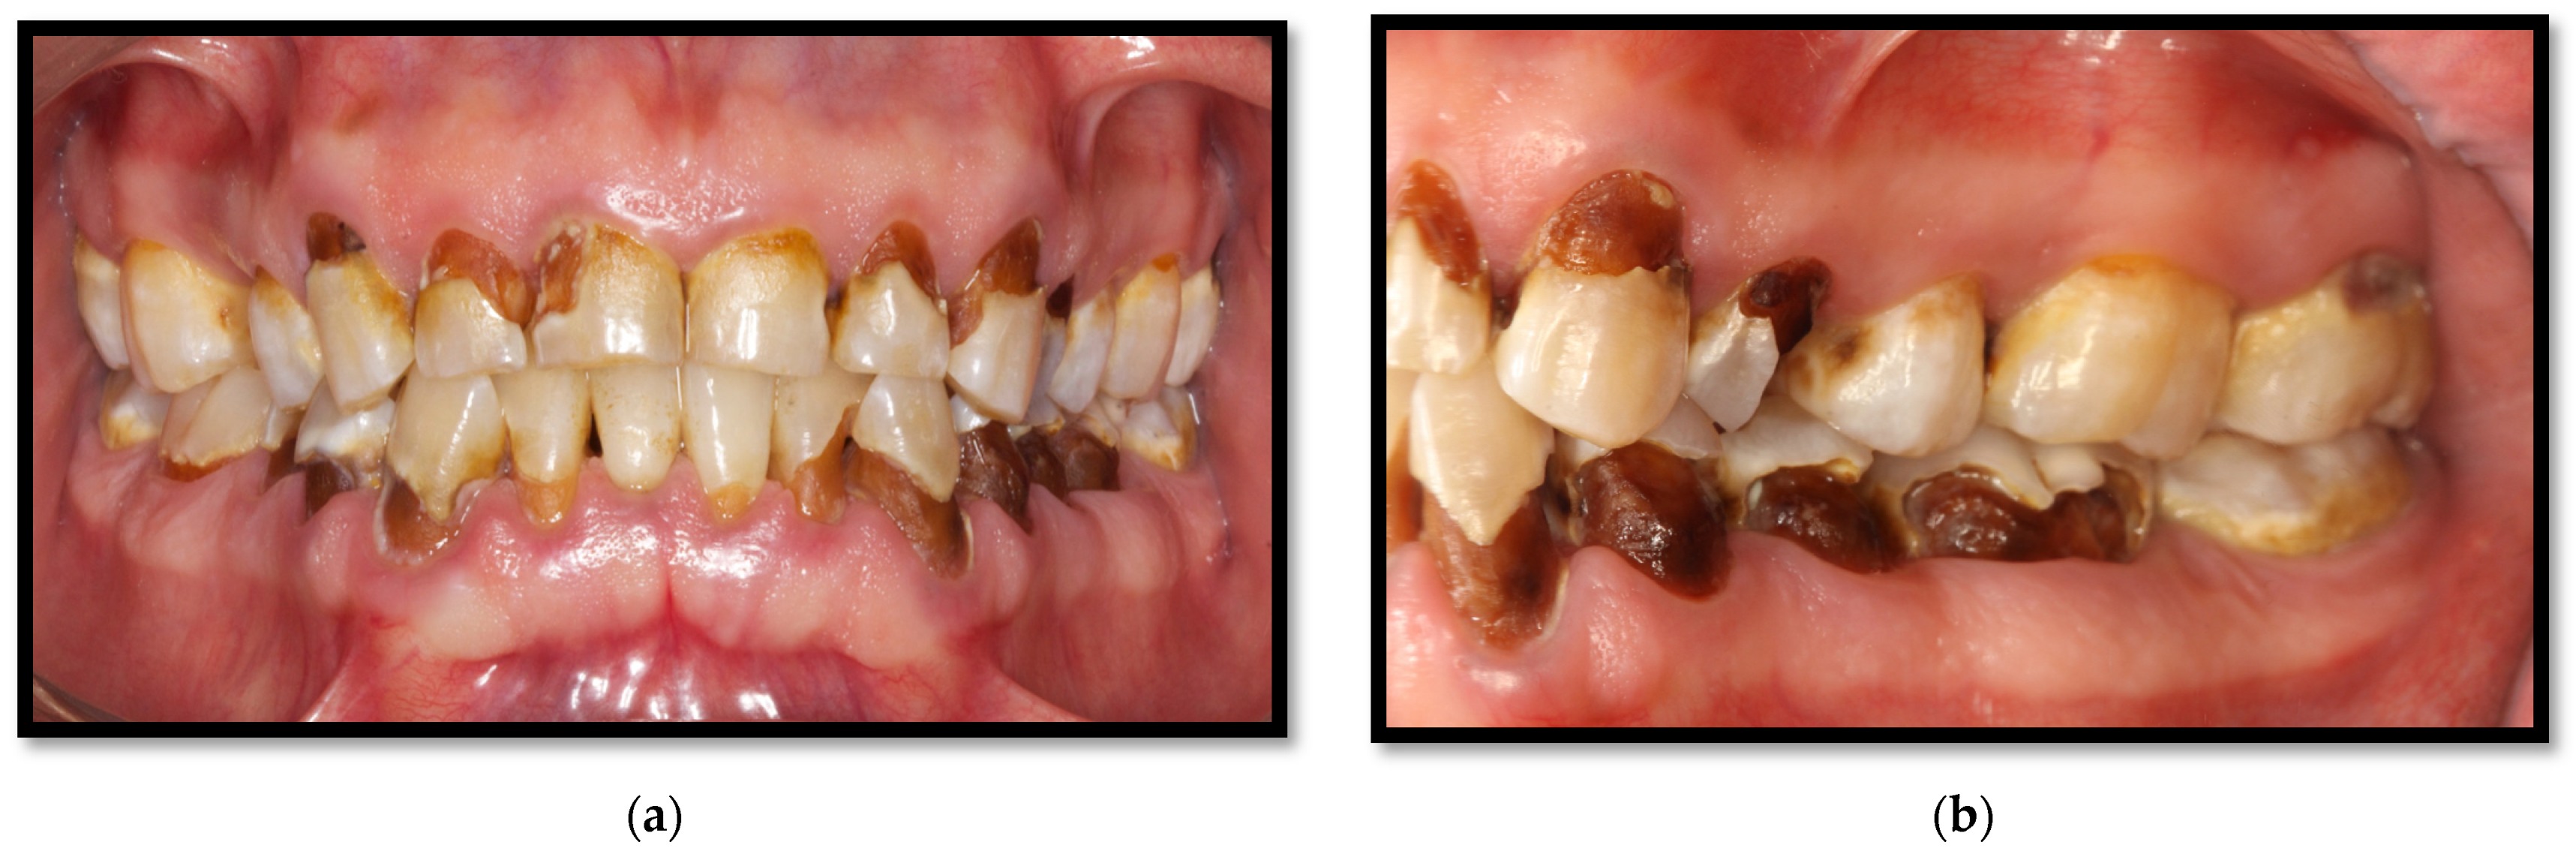

Dental caries is considered the most common oral disease in HIV-positive patients, with a prevalence reported between 54% and 83% [3,49,50]. It is a multifactorial disease triggered by the interactions of dental biofilm, skin surface, sugary diets, and the host’s vulnerability [2]. Bacteria on the biofilm involved in caries onset and progression, mainly Streptococcus mutans and Lactobacillus, respectively, metabolize sugars, thereby producing acid substances which that decompose enamel and dentin [10].

Caries can affect one or multiple dental surfaces; however, studies on the clinical characteristics and behavioral patterns of dental caries among HIV patients are scarce. Rezaei-Soufi et al. showed in their study a significant difference in the number of carious surfaces, including roots and crowns, in HIV-positive patients compared to HIV-negative patients. However, the prevalence of root caries is not significantly different between the two groups [51]. Additionally, it has been suggested that the severity of dental caries increases significantly with age and the duration of ART [51]. Within recent years, it has been suggested that C. albicans might increase caries development in patients who have HIV/AIDS, considering its capability to produce lactic acid through carbohydrate fermentation and hydroxyapatite dental structure degeneration processes, which is complicated with greater severity and the progression of caries development [10,11].

On the other hand, saliva has an essential role in preventing dental caries development due to its antibacterial and antifungal properties. It also possesses pH-buffering features within the oral cavity through bicarbonate and phosphate. As well, it provides necessary calcium and phosphate substrates to maintain dental enamel integrity. Lastly, saliva is also capable of producing antibodies [34]. HIV infiltration, CD8+ T lymphocyte proliferation within salivary glands, as well as antiretrovirals decrease the quality and quantity of salivary flow and modifies the normal oral cavity microbiome [8]; for this reason, these are considered the main risk factors for dental caries development in HIV-positive patients. Adding to the already mentioned predisposing conditions, suboptimal oral hygiene, tobacco use, drugs, periodontal disease, and a carbohydrate-rich diet are relevant factors leading to substantial dental caries development in this population (Figure 15a,b) [34,50].

Figure 15.

Multiple dental caries. (a) Front view, softened tissue in cervical and interproximal areas; (b) Lateral View, softened tissue in cervical areas.